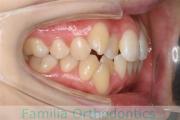

No.20V-496

- 叢生

- 年齢:

- 15歳

- 性別:

- 女性

- 抜歯部位

- 上:

- 84|58

- 下:

- 8558

全体的なでこぼこを治したいということで来院されました。上顎は右は4,左と下顎両側は5番を抜歯して、マルチブラケット法にて治療を行いました。2年強、25回程度の通院をしていただきました。

非常に強いでこぼこですので、後戻りのリスクは高めであると思われます。

- ≫治療前

-

上顎

下顎

前歯の関係など

右側

正面

左側